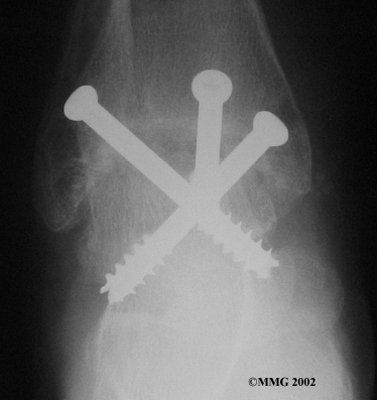

It is important when the surfaces are removed that the angles of the cut surfaces are correct. When the tibia is brought against the talus, the foot should be at a right angle to the lower leg. Once the cuts are made the bones must be held in place while they fuse. This can be done using large metal screws and metal plates if necessary. The screws are usually under the skin and are not removed unless they begin to rub and cause pain.

Inserting the screws

After ankle fusion, the physical therapists at FYZICAL South Hagerstown can help you learn to walk smoothly and without a limp. Although time needed for recovery varies among patients, an ankle brace will typically replace your cast after eight to 12 weeks. Your surgeon will take X-rays frequently to see if the bones are fusing together. You will probably need to use crutches during the time you wear the cast. As the fusion grows stronger, you will begin to put more weight on your foot when walking.